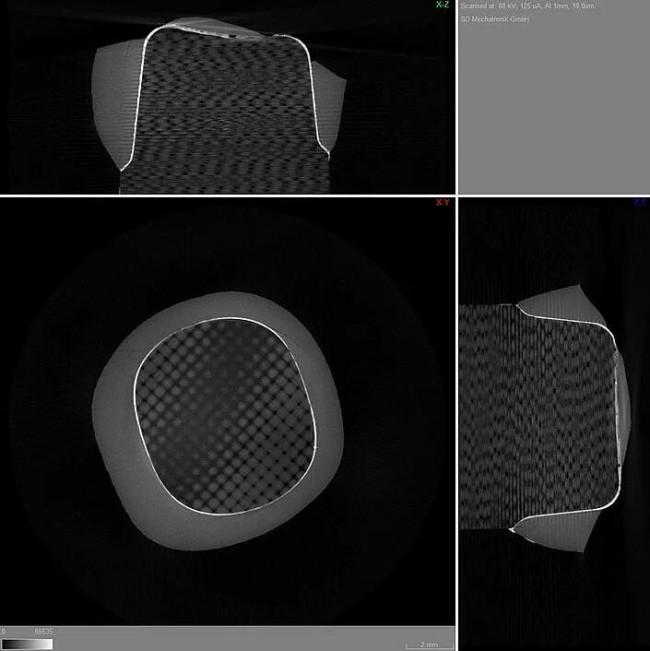

仿真完成后,胶合冠被从残端移出,研究人员测量了完成移除所需的力,并分析了损坏情况。研究人员使用微型计算机断层扫描(µCT)检查边缘间隙,并使用基于计算机的有限元分析(FEA)最终验证了结果的有效性。

- 既没有观察到冠缘的抬起,也没有观察到复合材料从边缘间隙被冲刷掉。µCT表明,在任何一种测试情况下,边缘间隙都没有增加,键合区域没有受到破坏,并且胎冠也没有由于机械载荷而发生移动。

FEA分析表明,在VarseoSmile Crown plus 材料3D打印牙冠边缘区域,没有可检测到的或没有临床相关的张力或变形。这一结果保证了3D打印牙冠与残端之间稳定、持久的边缘闭合。